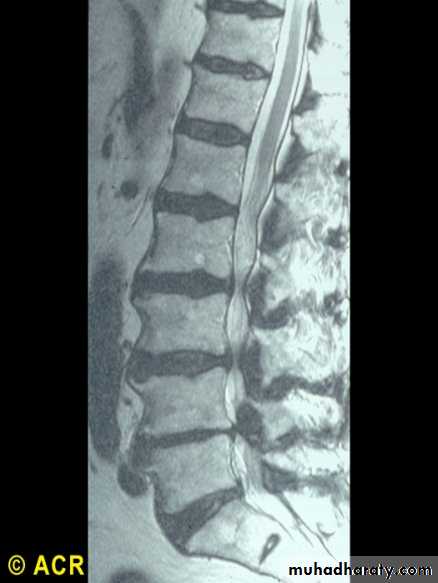

Spinal stenosis:lumbar spine(MRI) due toO.A.